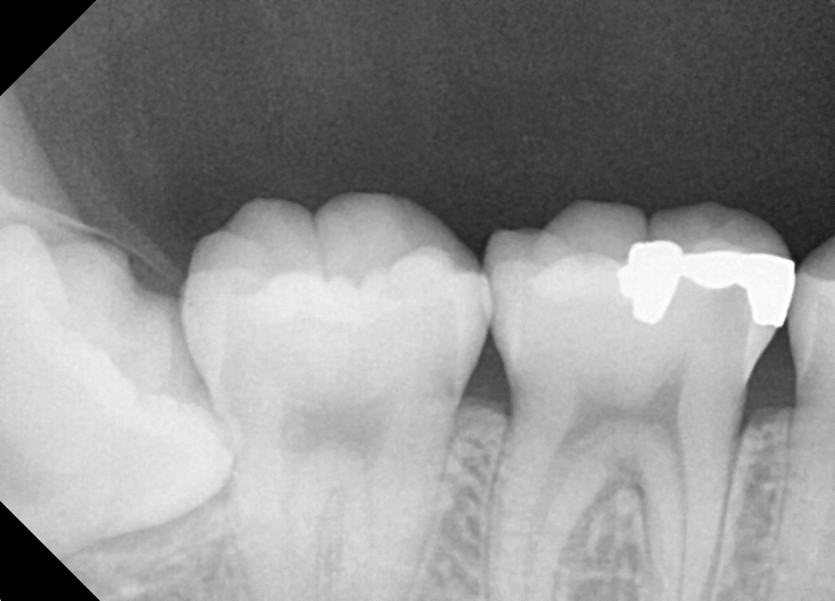

#38,48 사랑니 발치

구강 외과 전문의가 당일 발치했습니다.